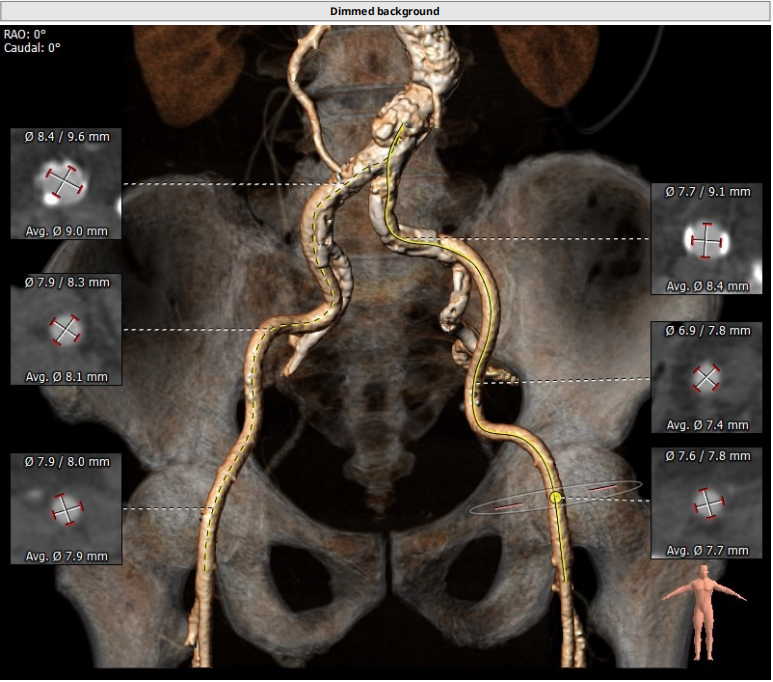

三叶瓣,重度钙化,钙化主要分布在瓣叶游离缘,法式窦结构较大,双冠高度较高,升主动脉未见明显扩张,心脏角度40°,左室大小可,心肌肥厚,主动脉弓部走行较平缓,主动脉弓部可见钙化,过弓轻柔谨慎,以右侧股动脉为主入路。

唐熠达教授团队对病例进行多学科综合分析评估决定行一站式PCI+TAVI手术,结合患者91岁高龄,主动脉根部结构及双侧劲动脉粥样硬化斑块形成,脑动脉硬化情况采用20mm球囊预扩,拟植入VenusA-Valve L26瓣膜。